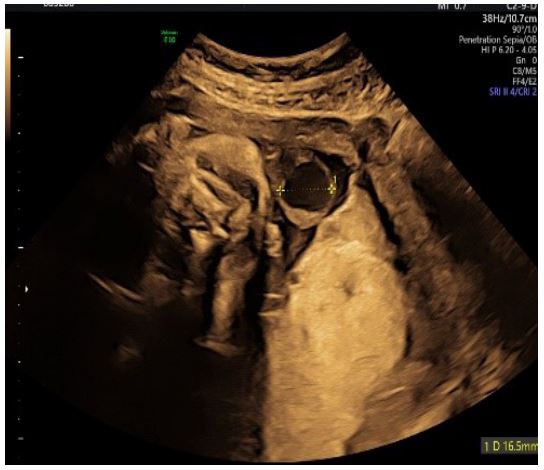

At 30 3/7 weeks of gestation, we first discovered an extra-abdominal varix of the umbilical vein with a diameter of 16.5 mm (Figure 3).

Figure 3: Transabdominal 2D ultrasound (transverse view) showing a dilated umbilical vein within the cord.